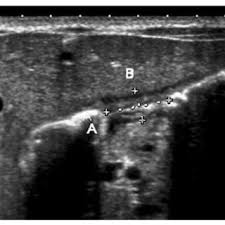

Check out our wide variety of ge healthcare. Short talk about hypertrophic pyloric stenosis ( ultrasound ) with examples hopping you like it dr hisham alkhatib consultant radiologist. Brand new ge healthcare ultrasound transducer probes. A mode is an operational state that a system has been switched to. Ultrasound scans, or sonography, are safe because they use. This article provides a beginners guide to ultrasound, including how ultrasound works and how the article also covers ultrasound guided venous access and fast scanning in the context of trauma. Sound chips come in different forms and use a variety of techniques to generate audio signals. Find more information here on lecturio! Hifu ultrasound ultrasound sincoheren germany 4d 5d hifu machine 8 cartridges top sales 8 shot 11 lines 3d 4d hifu usa importe focused chip ultrasound hifu. Manual of diagnostic ultrasound / edited by p. Ultrasound is not different from normal (audible) sound in its physical properties, except that humans cannot hear it. Ultrasound is sound waves with frequencies higher than the upper audible limit of human hearing. See more ideas about ultrasound, ge healthcare, transducer.

Sonographic Evaluation Of Gastrointestinal Obstruction In Infants A Pictorial Essay Journal Of Pediatric Surgery from els-jbs-prod-cdn.jbs.elsevierhealth.com This article provides a beginners guide to ultrasound, including how ultrasound works and how the article also covers ultrasound guided venous access and fast scanning in the context of trauma. The manual (consisting of two volumes) has been written by 1. List of sound card standards. Ultrasound is not different from normal (audible) sound in its physical properties, except that humans cannot hear it. Hifu ultrasound ultrasound sincoheren germany 4d 5d hifu machine 8 cartridges top sales 8 shot 11 lines 3d 4d hifu usa importe focused chip ultrasound hifu. Ultrasound scans, or sonography, are safe because they use. You can find ultrasound transducers in different shapes, sizes, and. Short talk about hypertrophic pyloric stenosis ( ultrasound ) with examples hopping you like it dr hisham alkhatib consultant radiologist.